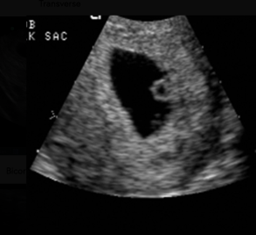

The gestational sac appears as an anechoic, round structure with an echogenic border

A key pitfall is the pseudogestational sac, which may resemble a gestational sac but lacks a yolk sac within it. A pseudogestational sac does not confirm an IUP and can be seen in patients with ectopic pregnancy.

The double decidual sign, characterized by two concentric echogenic rings (one surrounding the gestational sac and one lining the uterine cavity) can help confirm that the gestational sac is actually within the uterus as shown below.